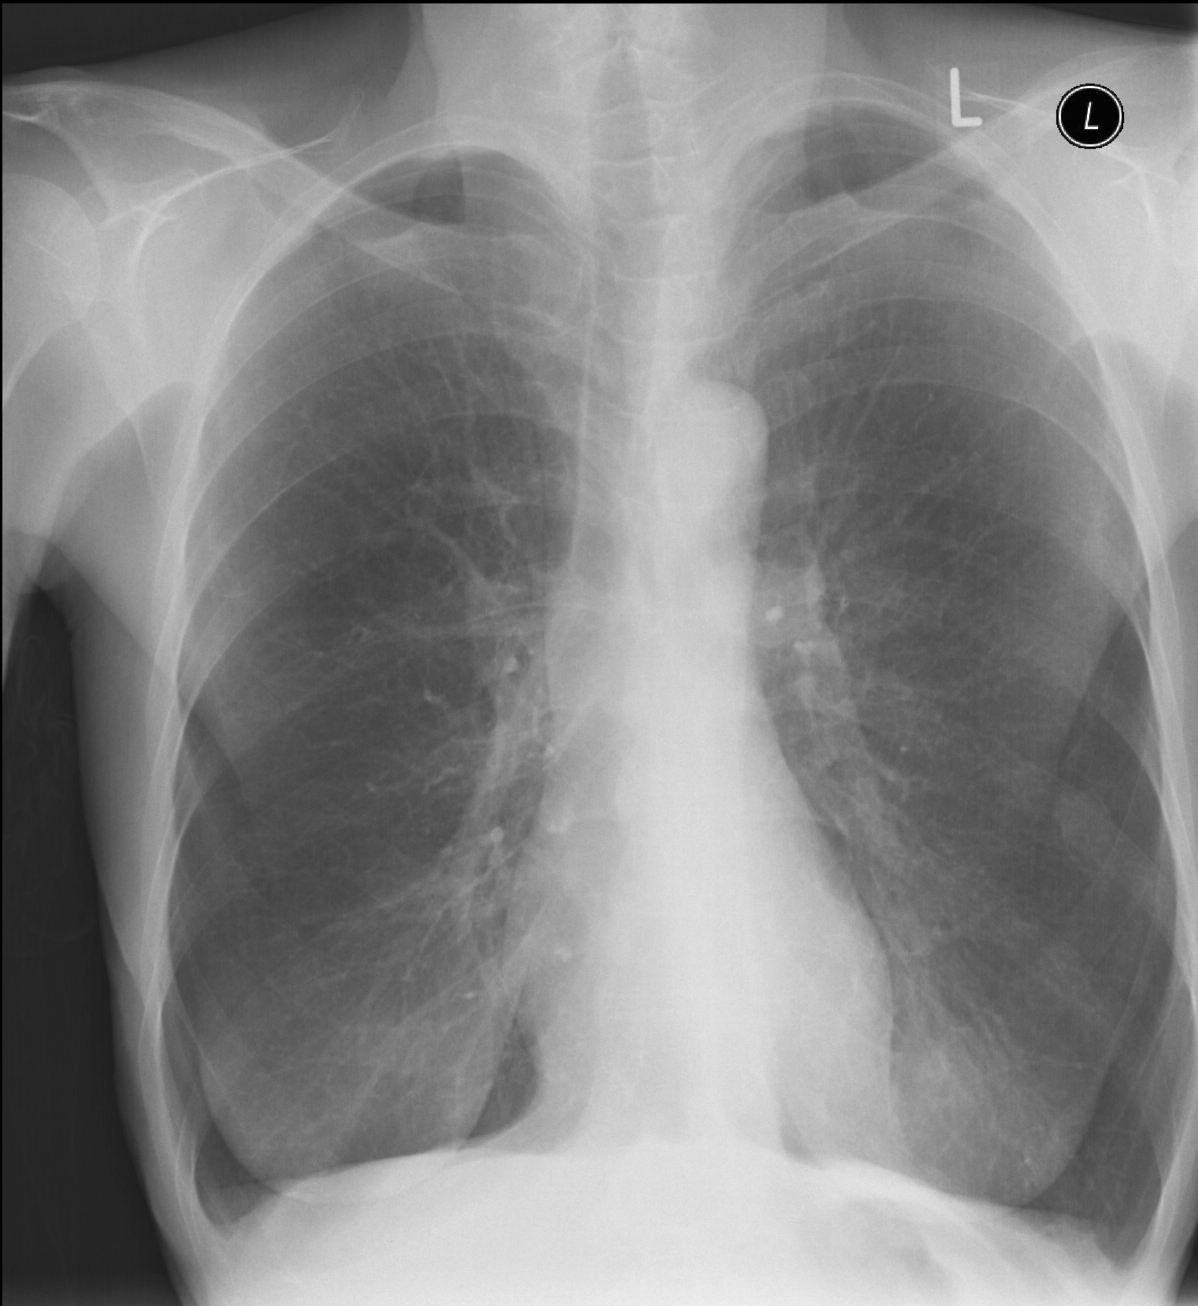

13: Emphysema, bilateral chest radiograph

90 year old woman, hx of breast cancer, secondary pulmonary disease, TB therapy.